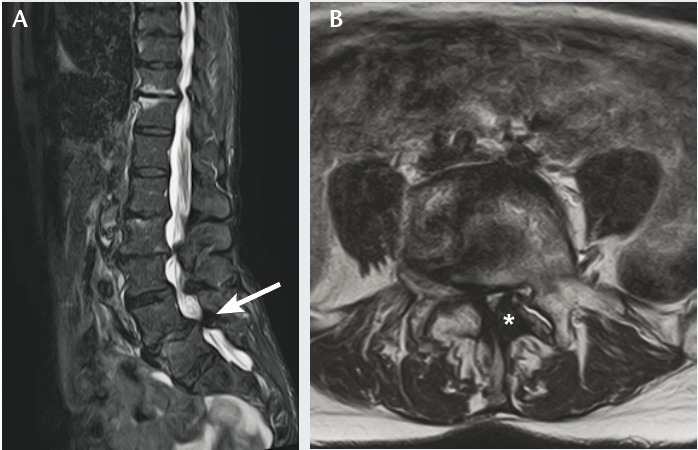

Diagnostic confirmé par IRM ou scanner du rachis lombaire :

– contrairement au canal étroit constitutionnel, la sténose est plutôt segmentaire (touchant 1 ou 2 étages seulement, fig. 2 et le plus souvent centrale (segment disco-articulaire) et latérale (défilé disco-articulaire, récessus latéral ou foraminal) ;